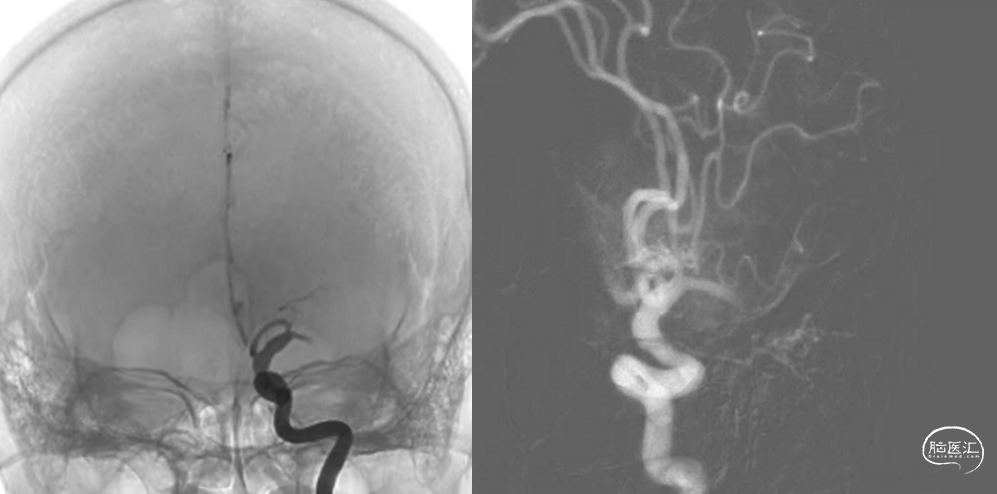

术前头颅CT+CTA:左侧基底节区及放射冠区腔隙性脑梗塞、双侧颈内动脉及基底动脉硬化、左侧大脑中动脉M1段以远闭塞。

左侧大脑中动脉M1段闭塞。

前、后交通动脉均未开放,未见后循环经软脑膜支代偿血运供应左侧颞叶。